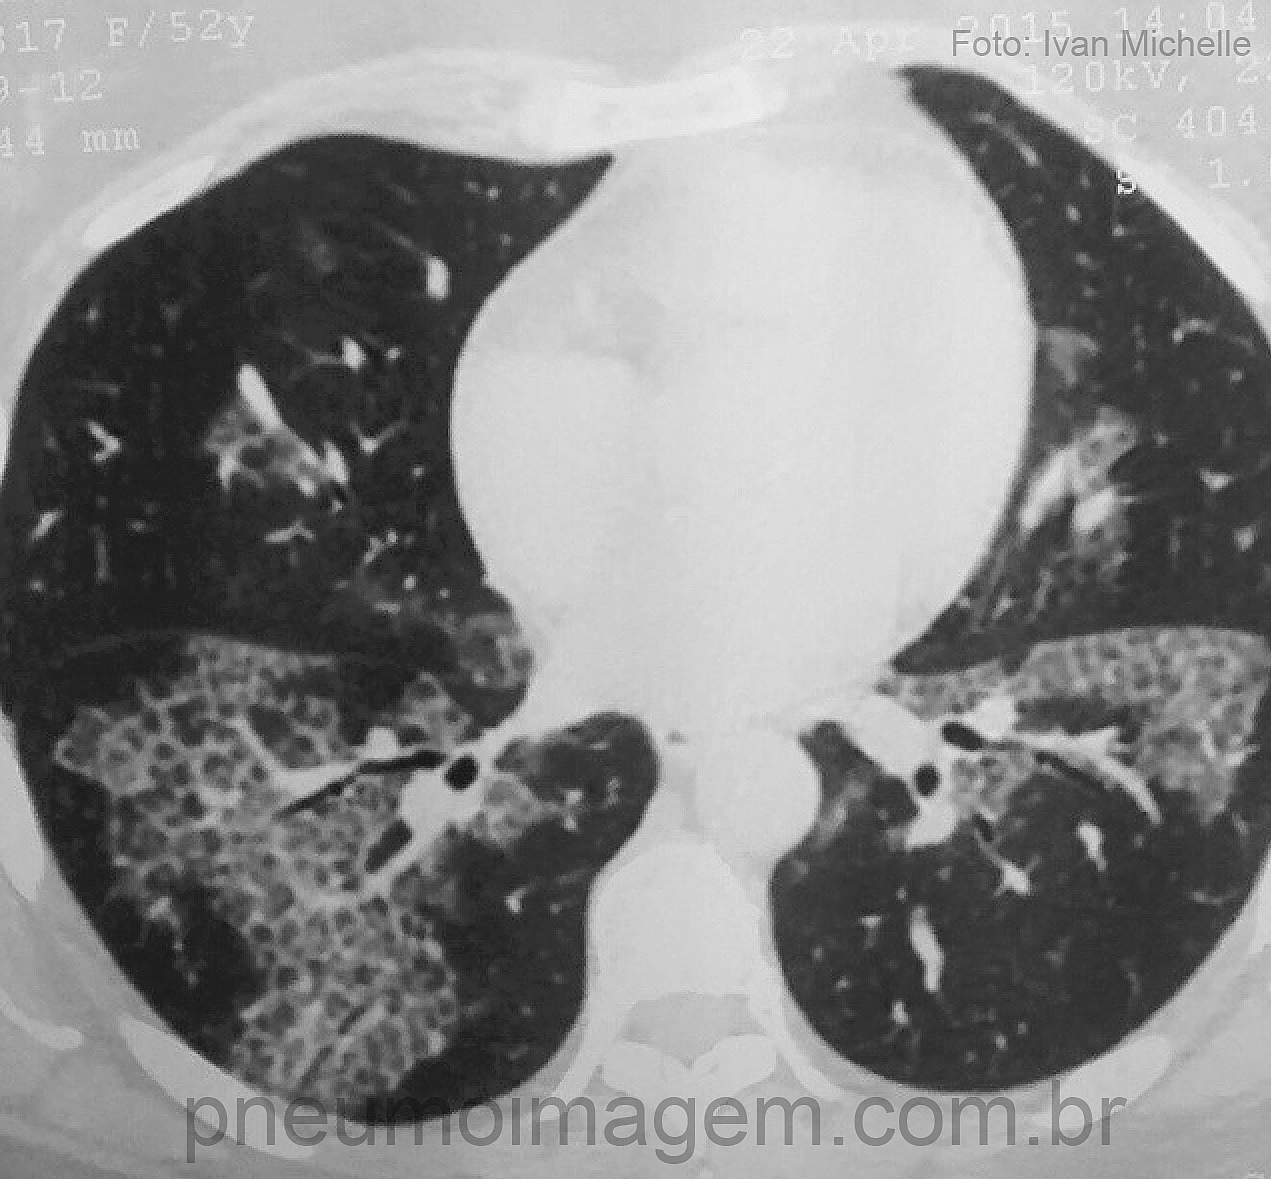

CASO CLÍNICO #27Abrimos espaço para o caso desse mês para o nosso seguidor do Instagram Ivan Michelle (@IVAN3MICHELLE), que nos enviou essa imagem interessante e pediu a opinião dos nossos amigos. Paciente do sexo feminino, 52 anos. Qual o diagnóstico mais provável? Deixe os seus comentários abaixo.

The clinical case of the month was sent by our Instagram follower Ivan Michelle (@IVAN3MICHELLE), who sent us this interesting image and asked the opinion of our friends. Female patient, 52 years-old. What is the most likely diagnosis? Give your comments below.

Proteinose Alveolar